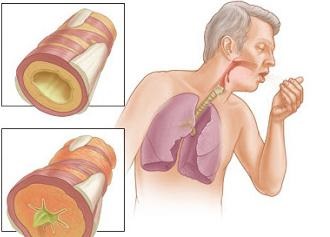

Biztos vagyok benne, sokan tudják, hogyan teremthettek hurutok. Mi ez azonban gyakran nem ad egyértelmű választ. Tehát, ez egy gyulladásos folyamat a nyálkahártya a légcső, a tettes baktériumok és vírusok. Szintén betegség fejlődhet ki, mint a kedvezőtlen fizikai (hideg vagy meleg levegővel), vagy kémiai expozíció. A gyulladásos folyamatot kíséri extenzív duzzanat a nyálkahártya a kibocsátást a gennyes váladékot. Ez egy akut és krónikus hurutok.

Ez egy gyulladásos reakció, amely akkor fordul elő a bélés a légcső, általában az okozza, egy vírusos fertőzés, staphylococcus, de a legtöbb pneumococcus. Trigger a fejlesztés a patológiai a betegség lehet a krónikus orrmelléküreg, gyakori hipotermia, alkohollal való visszaélés és a szívbetegség. Egy tipikus tünet a száraz görcsös köhögés, rosszabb a reggel, és közben egy mély lélegzetet, sírás vagy a hőmérséklet változása.

Ezzel csatlakozik a fájdalom a torokban és a szegycsont, károsodott légzés (sekély, gyors). Köpet, amely felhalmozódik a hörgőket, irritálja a légzőrendszert, ami szamárköhögés. Talán egy kicsit láz, a negyedik napon van bőséges váladék. Annak érdekében, hogy elkerüljék a szövődmények kell megfelelően kezelni hurutok.

Ez a forma jelenik meg eredményeként vulkanizálatlan akut hurutok. A jellemző egy súlyos, hosszú passzok, köhögés, rosszabb éjszaka. Vannak fájdalom a mellkasában, mint a tüdőgyulladás. Köpet viszkózus, fel kis mennyiségben, lehet gennyes. Megbetegedést szemrevételezéssel és az eredmények laringoszkópiával.